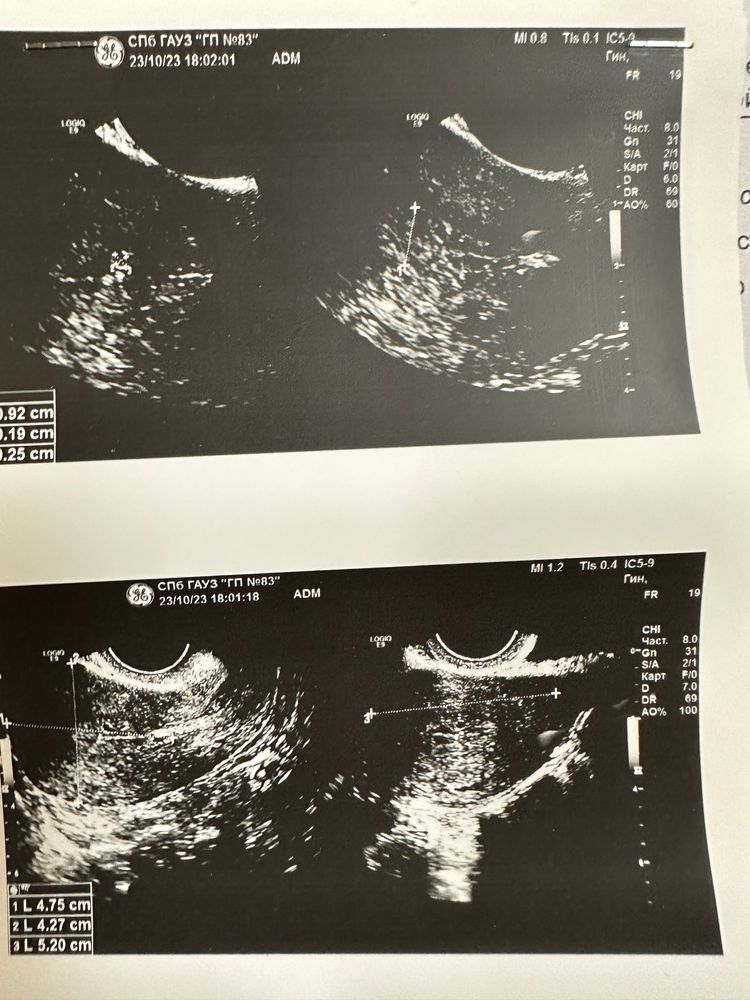

Тест отрицательный- беременности нет. На узи кисты яичников

У вас на фотографиях яичники